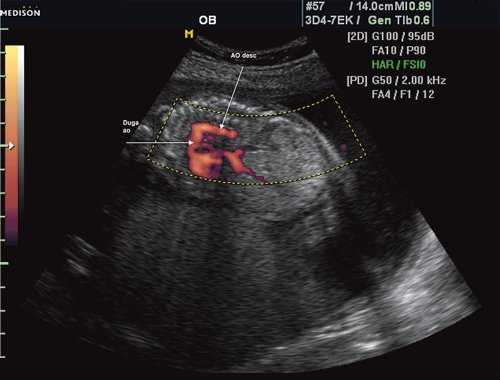

Рис. 1. Восходящий отдел, дуга и нисходящий отдел аорты плода в режиме энергетического допплера в норме.

Ключом к пренатальной диагностике коарктации аорты является комплексный учет данных, получаемых как при изучении четырехкамерного среза сердца (дилатация правого желудочка, гипоплазия левого желудочка), так и при оценке самих главных артерий. При наличии коарктации диаметр аорты в среднем в 2 раза меньше диаметра дилатированной легочной артерии. Поэтому для диагностики коарктации аорты следует использовать визуализацию самой аорты, что наиболее целесообразно при скрининговой оценке среза через три сосуда. Помощь в диагностике может оказать измерение диаметра артериального протока, который при коарктации аорты широкий.

Окончательный диагноз коарктации аорты устанавливается при использовании среза через дугу аорты, так как чаще всего сужение аорты отмечается в области ее перешейка - на уровне впадения артериального протока. Следует отметить, что сужение может охватывать большой участок аорты вплоть до тубулярной гипоплазии. Нормальный переход дуги аорты в артериальный проток в норме гладкий и плавный. Кроме того, при исследовании аорты по длинной оси наиболее надежным признаком следует считать гипоплазию поперечной части дуги аорты. Как один из косвенных признаков коарктации аорты можно использовать извилистость дуги аорты при изучении ее по длинной оси [2].

Важное дополнительное значение имеет допплерэхокардиографическое исследование, которое при коарктации орты позволяет выявить ускорение и турбулентный характер кровотока в аорте. Однако в антенатальном периоде этот признак может не проявиться [2]. Более надежно выявление левоправого шунта через овальное окно. Предполагается, что этот шунт является компенсаторным механизмом, обеспечивающим уменьшение потока крови в левый желудочек и аорту. G. Sharland и соавт. [18] отметили левоправый шунт через овальное окно у 7 из 12 плодов с коарктацией аорты. У оставшихся 5 плодов обнаруживалось как левоправое, так и праволевое направления потоков крови через овальное окно.